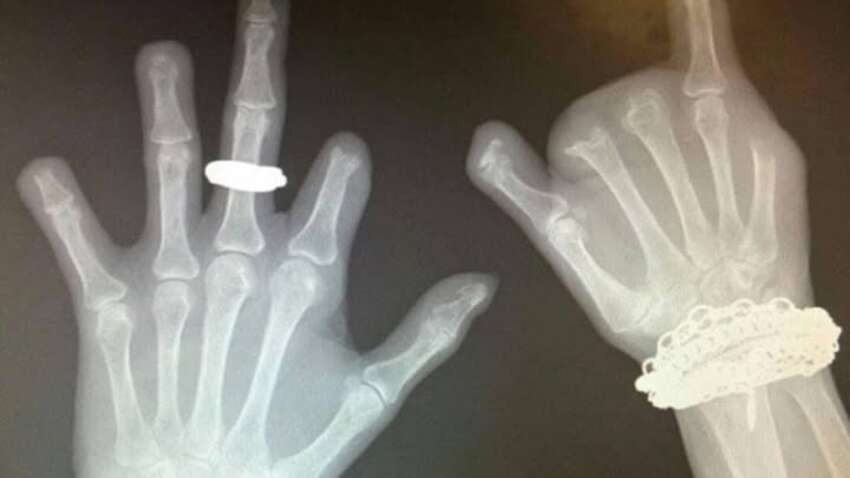

Медики показали вражаюче фото та клінічний випадок, який ще раз доводить: звичка гризти нігті — це не просто невинний жест нервозності. У пацієнтки, яка роками страждала на тяжку форму оніхофагії, постійне пошкодження нігтів переросло у хронічні рани, бактеріальні інфекції та зрештою — остеомієліт. Ураження кісток було настільки серйозним, що хірургам довелося ампутувати кілька фаланг пальців. На рентгенівських знімках чітко видно деформації та відсутність частини кісток. Про це повідомляє “Типовий медик”.

Наслідки тяжкої оніхофагії: інфекції, деформації та ампутація кількох пальців.